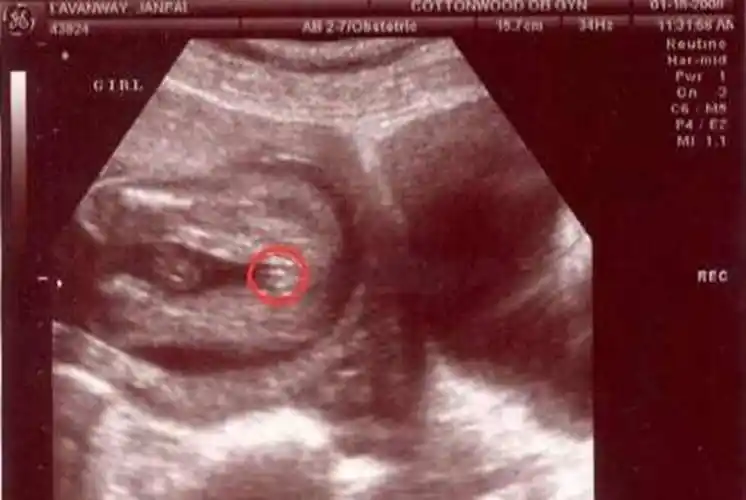

品冠晒出老婆b超照

b超大排畸能看胎儿性别吗?

快拿出b超上的照片,教你怎么自己看孩子性别,大夫也是这样判断_胎儿